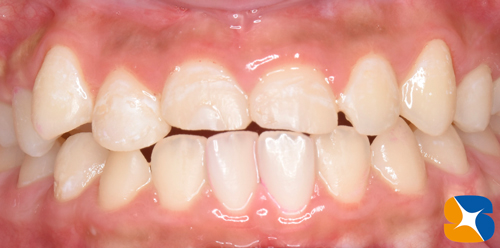

事故から7ヶ月後の今年4月(令和5)、固定装置を取り除きました。嬉しい事に前歯の固定が認められました。

お子様をはじめ、ご両親の協力とご理解のもと、事故で歯を失いかけた状態から復元させることが出来ました。